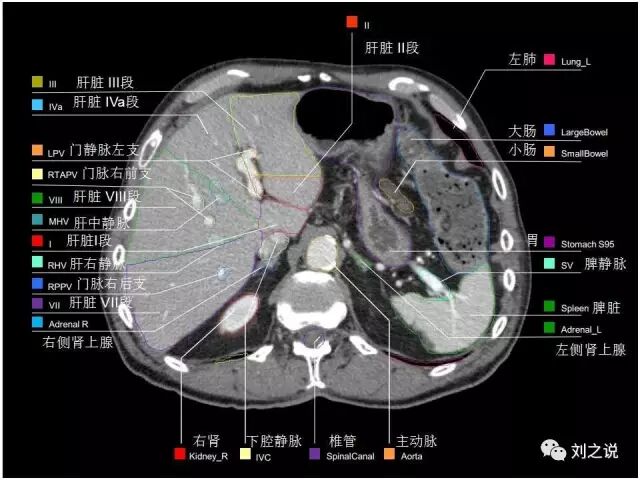

【解剖】高清实用 腹部CT断层

参考RTOG共识和3D-body解剖。

来源:刘之说